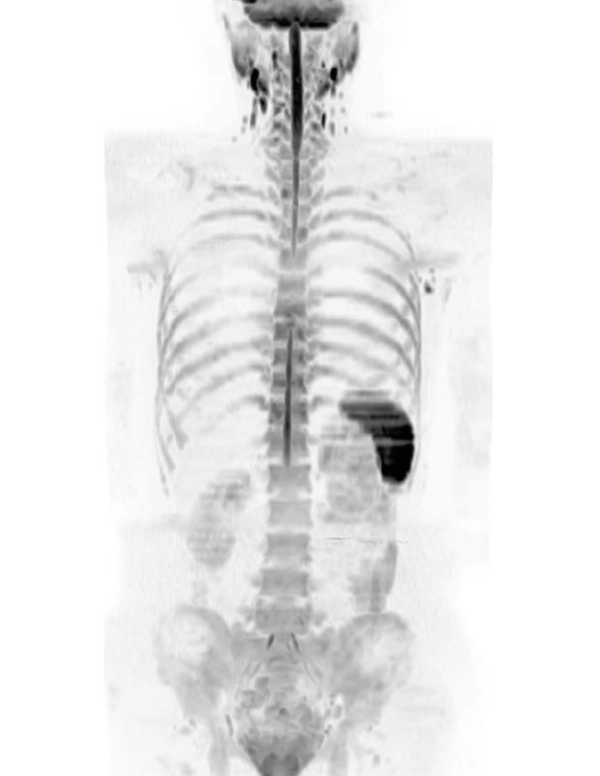

Wide coils:Keep patient within imaging range

DWI AX (MIP)

3.7×3.1×5.0 mm

3st total scan time 7:25

3D T1WI COR

2.2×1.5×1.5 mm

3st total scan time 0:54

Lower extremity

non-contrast MRA (MIP)